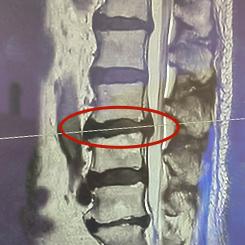

熊女就是“忍一忍”的受害者之一。每一次疲劳之后,熊女人都会感到左下肢酸痛,并伴有麻木。起初熊女人并没有放在心上,强忍着这种痛苦。后来疼痛明显加重,导致她无法下床活动,严重影响了日常生活。直到那时,无法忍受的熊女士才来到奉贤区中心医院骨科寻求医生的帮助。结合症状体征和影像检查,医生诊断熊女士为“腰椎间盘突出症”,接受住院治疗。

住院后,熊女性经过层层保守治疗和腰脊神经阻滞治疗,病情无法缓解。在与熊女性及其家属充分沟通之后,制定了详细的手术方案。脊柱外科专家赵必增教授,位于上海市第六人民医院骨科中心,在局麻下为患者进行椎间孔镜下椎间盘切除。 神经根减压手术。手术时间不到一小时,熊女性在手术过程中已经感到疼痛立即缓解,术后第二天就可以自己下床走路了。

椎间孔镜技术是目前脊柱手术中最微创的技术,可以解决腰椎间盘突出引起的神经压迫引起的腰腿疼痛,只需要8mm的微切口。与传统的开放手术相比,椎间孔镜技术具有创伤小、疗效好、恢复快的优点。近年来,椎间孔镜技术逐渐扩展到颈椎和胸椎,取得了令人满意的临床效果。